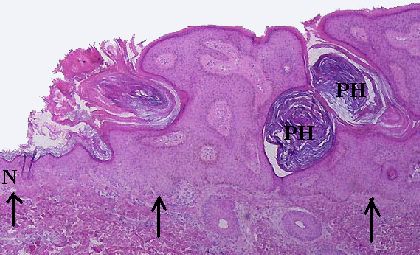

A seborrheic keratosis with an exophytic appearance. The base of the lesion is

level (arrowed) with the normal epidermis (N) on the left. Two pseudohorn cysts

(PH) are seen here which are formed from infoldings of the epidermis.

• the base of the seborrheic keratosis is flat and level with the base of the adjacent normal epidermis (ie. an exophytic appearance if the adjacent normal epidermis is included)

• acanthosis (thickening of the epidermal layer; in seborrheic keratosis this results from basaloid cell proliferation. Dysplasia is absent)

• hyperkeratosis (excess keratin)

• epidermal cysts filled with keratin (horn cyst) are common, some of these cysts resulted from infoldings of the epidermis (pseudohorn cysts).